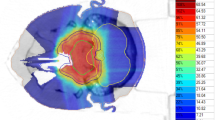

Patients were immobilized using a thermoplastic head mask system. All patients received computed tomography (3-mm slice thickness) for three-dimensional treatment planning. For exact contouring of the treatment volume and organs at risk, a three-dimensional correlation with contrast-enhanced T1-weighted and T2-weighted (T2-STIR) magnetic resonance imaging (MRI) was performed, which was then rigidly registered on the CT scan. All patients had macroscopic residual disease. Compression of the brainstem was present in 38%, contact without compression in 18%, and no contact but less than 3 mm distance in 16%.

For the boost clinical target volume (CTV2), a margin of 1–2 mm was applied to the gross tumor volume (GTV). The primary clinical target volume (CTV1) contained CTV2 and the preoperative tumor extent. Both PTVs (PTV1 and PTV2) were formed by adding a safety margin of 3 mm to the corresponding CTV. The Siemens Syngo PT Planning software (Siemens Healthineers, Erlangen, Germany) was used for treatment planning. The treatment was performed at the HIT in Heidelberg, Germany, using protons and carbon ions in active raster scan technique. Dose distribution was calculated using the local effect model 2 (LEM2). Dose constraints to OARs were prescribed according to the QUANTEC database, particularly the brainstem was limited to a maximal dose of 59 Gy (RBE; EQD2) [16]. If dose prescription goals and dose constraints could not be met at the same time, underdosage of the target was preferred. Detailed information concerning carbon ion treatment has been published previously [17].

A total of 111 patients received carbon ion treatment (C12) with a median total dose of 66 Gy (RBE; 45 Gy to PTV1, 21 Gy to PTV2) in a fractional dose of 3 Gy (RBE) six times per week (treatment on Saturdays). The remaining 36 patients received proton treatment (H1) with a median total dose of 74 Gy (RBE; 50 Gy to PTV1 and 24 Gy to PTV2) in 2‑Gy (RBE) fractional doses six times per week. If the total median dose of hypofractionated carbon ion therapy is calculated in EQD2 with an alpha/beta value of 10, the total dose is 71.5 Gy, and thus comparable to the proton dose of 74 Gy (RBE).

The treatment of skull base chordoma is particularly difficult because of the proximity to a number of organs at risk. Especially relevant are the optic system, with visual impairments as a side effect, and the brainstem as the center of vital functions, which need to be preserved at all cost. Depending on the proximity of the tumor to these organs, especially the brainstem, a local underdosage of the tumor with a possibly higher risk of recurrence has to be accepted, probably resulting in inferior local control. Increasing evidence for this suggestion has emerged in recent years. For example, Takagi et al. reported on 24 patients treated with protons or carbon ions and observed a marked reduction in 5‑year local control (81% vs. 100%) in patients with close proximity of tumor and brainstem, although this difference was not statistically significant. Guan et al. reported on 91 patients with skull base or cervical chordomas treated with protons, carbon ions, or combinations of both, and observed significantly reduced LC, PFS, and OS in patients with compression of brainstem or the optic apparatus [32]. Weber et al. found worse local control and overall survival in a mixed cohort of skull base chordomas and chondrosarcomas if tumor compressed the brainstem or optic apparatus [29] and Iannalfi et al. reported similar results in their prospective trial using protons or carbon ions for skull base chordomas [27]. These findings are augmented by a recent analysis of Basler et al., who saw the majority of recurrences in the area of the brainstem in a mixed collective of chordoma and chondrosarcoma and were able to show a compromised dose distribution in those areas in their dosimetric analysis [33].

In our cohort, we strictly applied our predefined dose constraints especially for brainstem (59 Gy EQD2 based on the QUANTEC data), accepting possible target volume dose restrictions. Consistently, we found significantly inferior local control and a trend toward inferior survival in patients with tumors located less than 3 mm from the brainstem, if treated in a primary situation. Surprisingly, no marked differences were observed in patients treated in a recurrent situation, although this might be driven simply by the much smaller sample size of recurrent cases.